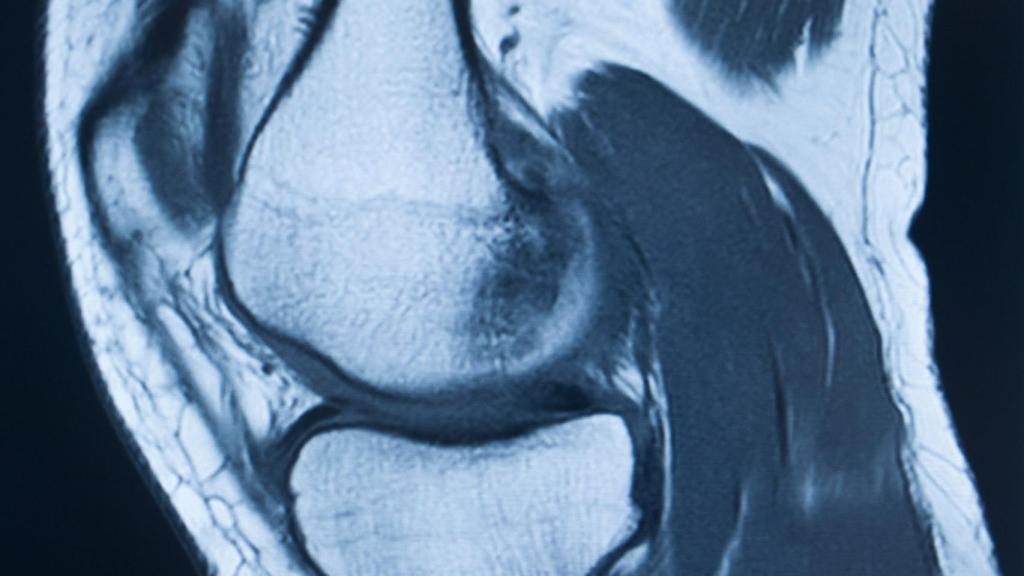

Imagen médica de una articulación de rodilla.

El Instituto de Biomecánica (IBV) está trabajando en un proyecto de investigación que permitirá, entre otros, la mejora del diagnóstico de enfermedades y lesiones mediante la inteligencia artificial (IA). Esta tecnología, además de reducir el tiempo y los recursos destinados para esta tarea, permite también un funcionamiento más óptimo del entorno hospitalario, lo que redunda en una mejor atención sanitaria.

En concreto, IBV está investigando en el modo de realizar el análisis de las imágenes médicas, que se utilizan para diagnosticar a los pacientes. Para ello, el centro ha desarrollado metodologías de cribado o preclasificación de patologías osteoarticulares, para la detección de lesiones, mediante la utilización de técnicas de inteligencia artificial.